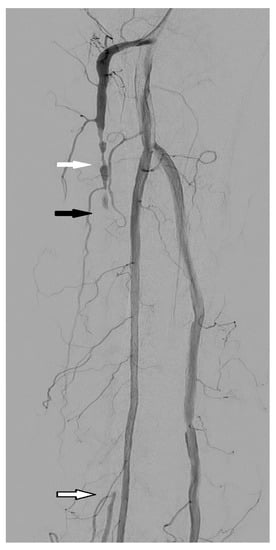

3.1. Stenosis and Occlusion

3.2. Dissection

3.3. Arteriovenous Fistula

3.4. Aneurysm and Pseudoaneurysm